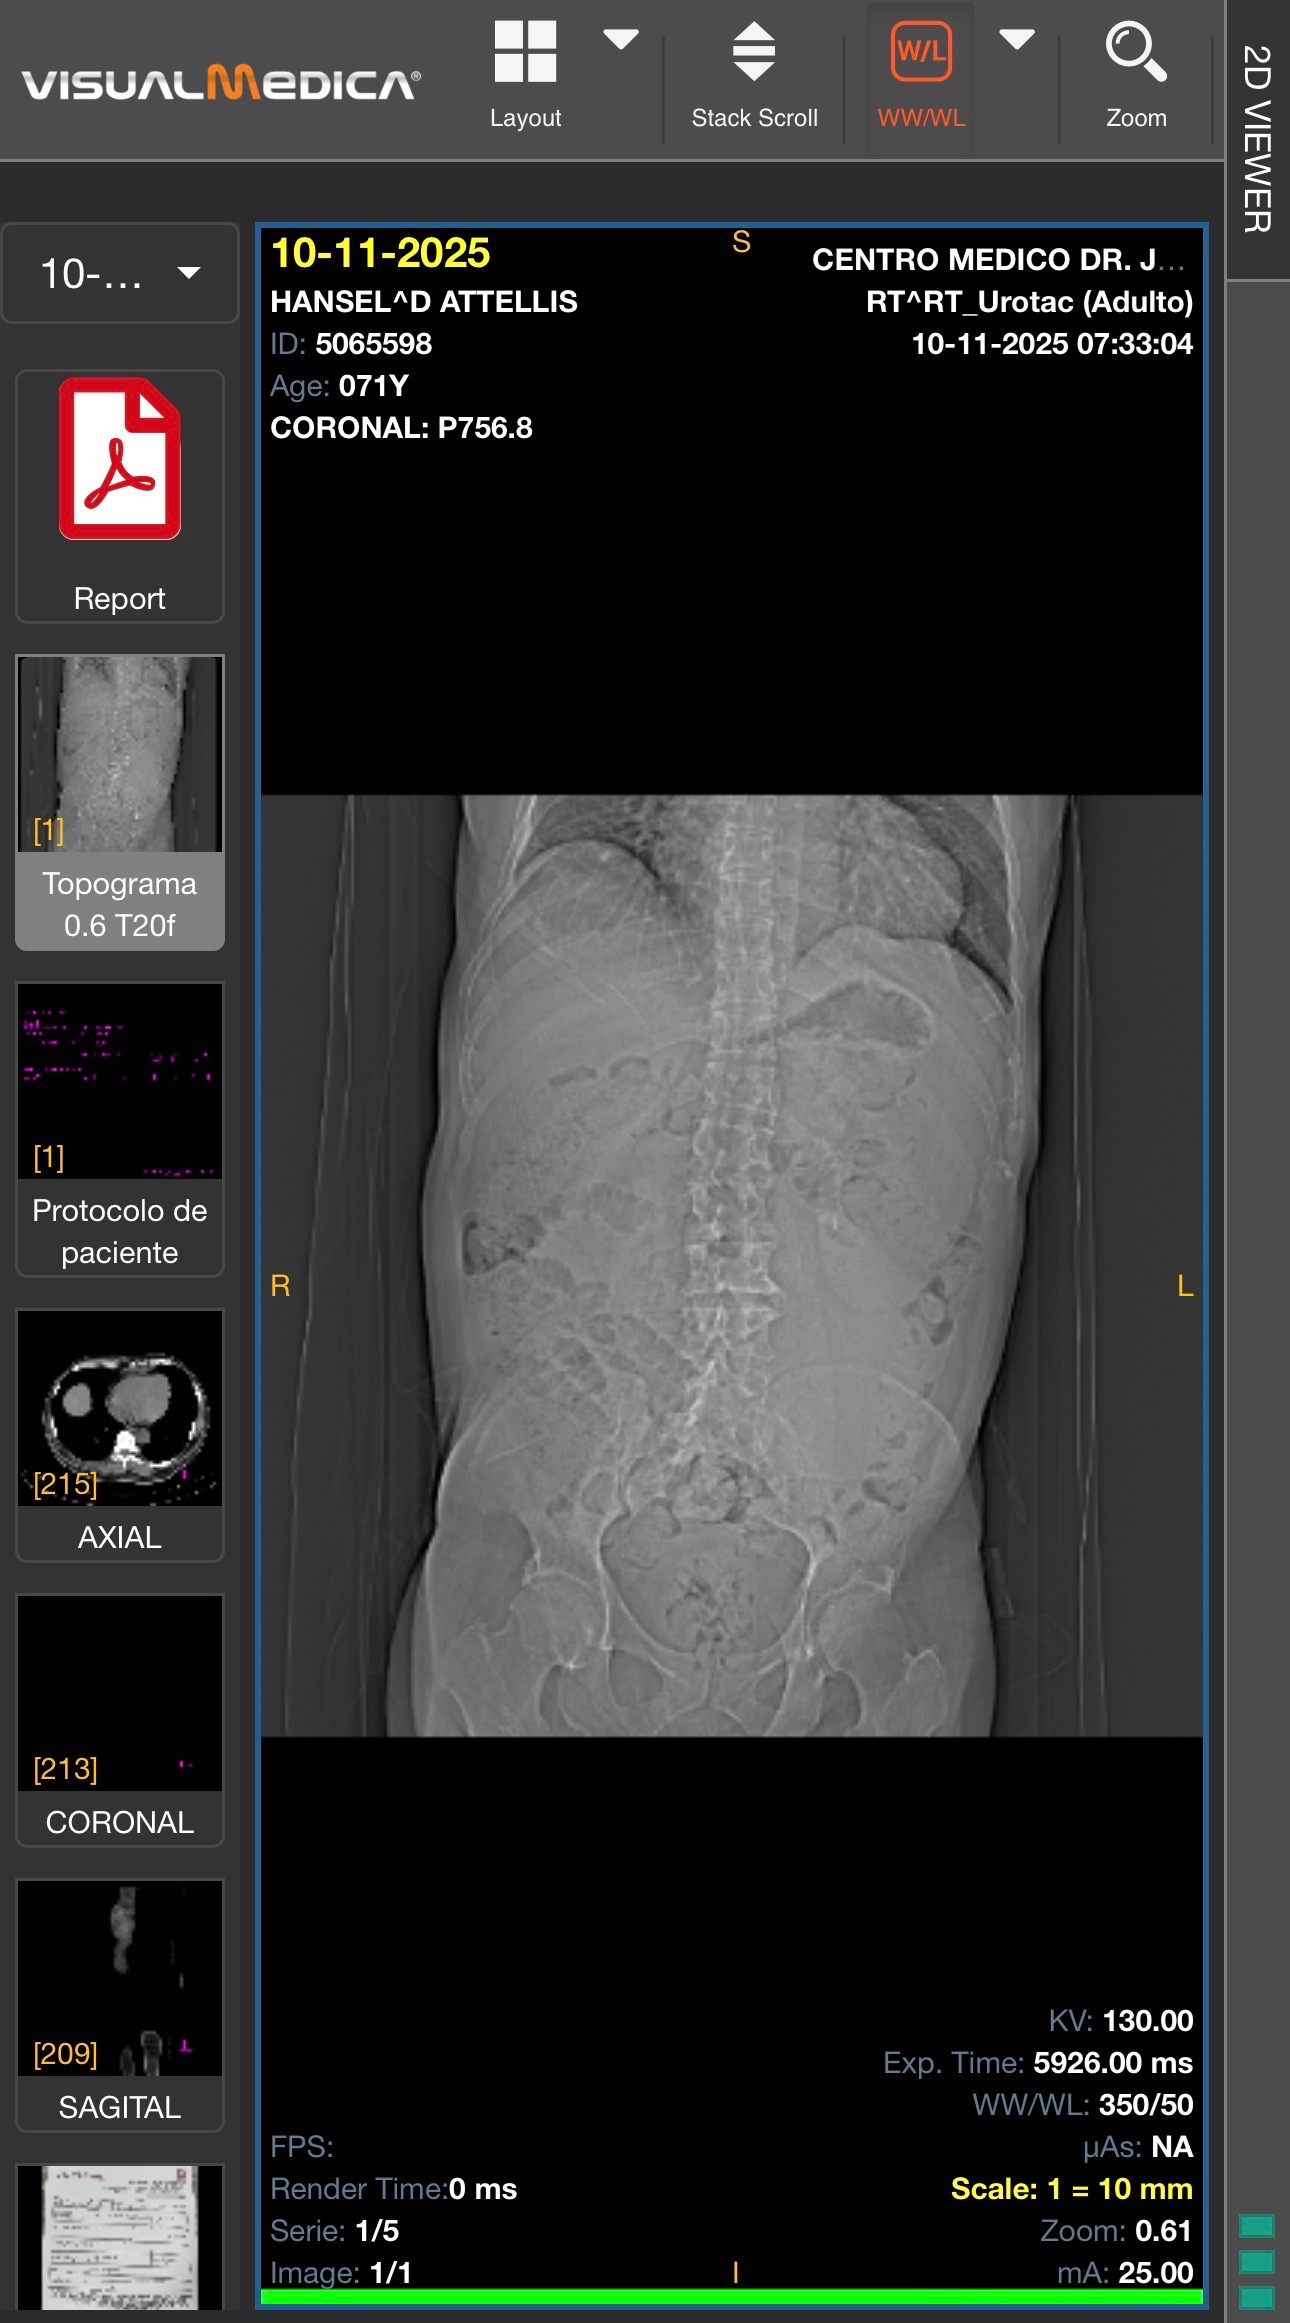

• Un quiste renal gigante en el riñón izquierdo (Bosniak II)

• Quistes múltiples en ambos riñones

• Riñón en herradura (malformación congénita)

• Hidronefrosis bilateral

• Atrofia del riñón derecho